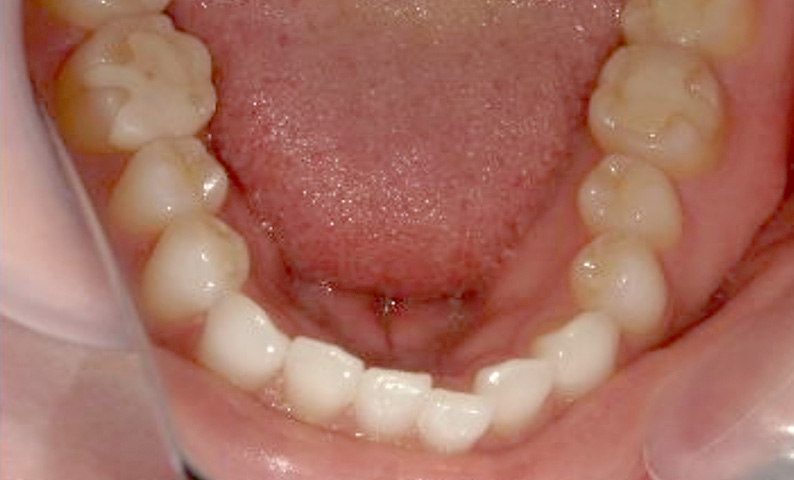

症例_030 上下顎の部分矯正

治療期間:12ヶ月金額:54万円+税女性八の字/V字型捻転歯前歯のガタガタ

| Before | After |

|---|---|

|